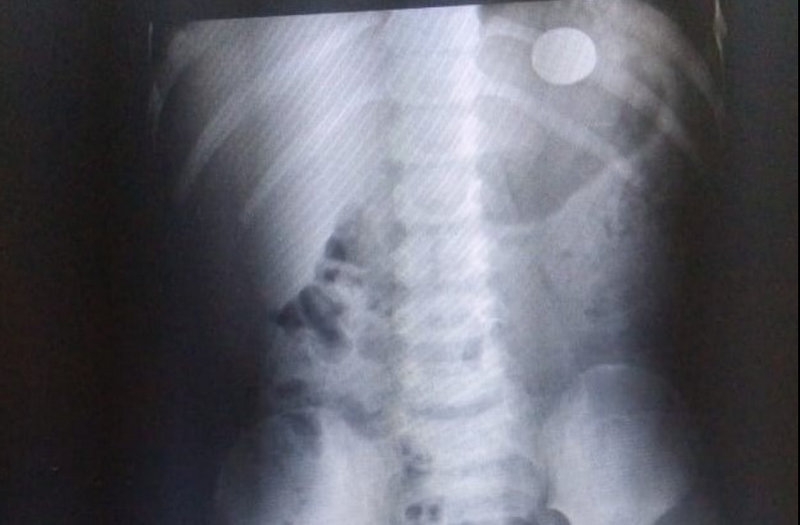

Porém, só descobriu que a criança havia engolido o objeto quando ela começou a se queixar de dores. Após Raio X feito na UPA da cidade, foi constatado que a moeda estava na barriga da criança.

O garoto engoliu a moeda no dia 9 (domingo), mas o objeto não se moveu para o intestino e se isso persistir, o menino poderá ter que passar por um procedimento cirúrgico para retirada.